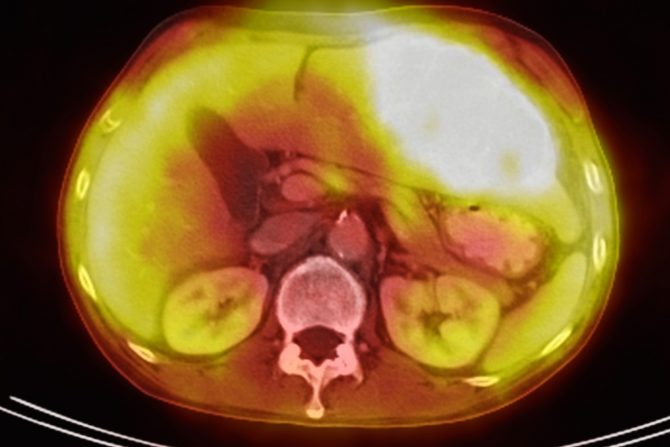

Metastatski rak jetre, koji se naziva i rak jetre stadijuma 4,  je uznapredovala bolest koja je započela u jetri, ali se proširila na druge delove tela. Dok putuju kroz limfni sistem ili krvne sudove, ćelije raka mogu da se šire po celom telu i počnu da napadaju nova tkiva ili organe u procesu koji se zove metastaza.

Iako se ovi pojmovi često mešaju, metastaze u jetri razlikuju se od metastatskog raka jetre. Metastaze na jetri su karcinomi, koji su se proširili (ili metastazirali) na jetru iz tumora koji je započeo u drugom delu tela, najčešće debelom crevu ili u rektumu, dok je metastatski rak jetre karcinom, koji se razvio u jetri i proširio na druge delove tela.